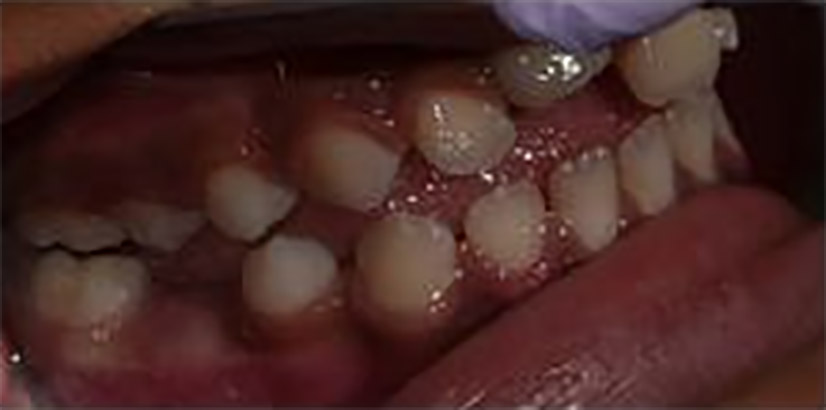

Figures 4,5 & 6: Posterior right, anteriors, and posterior left

Figures 17-21: Post operative photos after completed tx plan